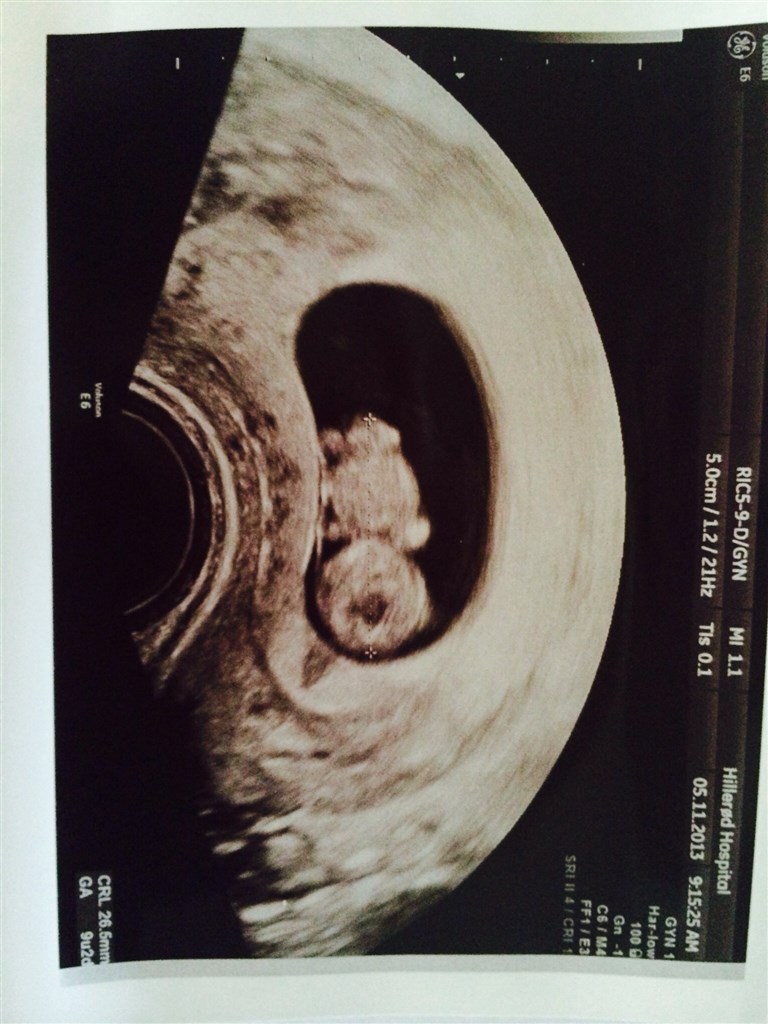

Har her til morgen været til ekstra scanning, da ts i uge 7 viste 2 små "fostre". Den ene målte dog kun 5 mm hvor den anden målte 13. De havde begge hjerter der slog, men da klinikken gerne ville følge udviklingen i den lille skulle jeg scannes igen.

Billede nr 1 viser størrelses forskellen på de 2 fostre, og nr 2 viser vores lille fis.